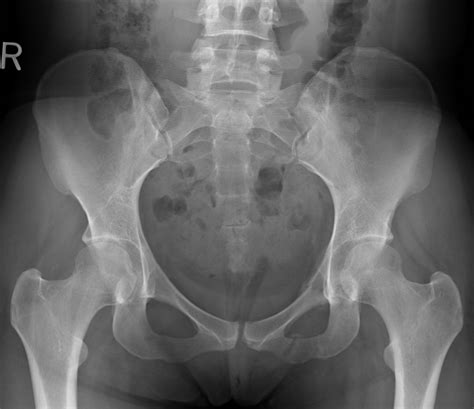

Normal Hip X Rays are a type of radiographic imaging used to visualize the hip joint and surrounding structures. This non-invasive procedure helps diagnose a wide range of conditions, including fractures, dislocations, arthritis, and developmental issues. The hip joint is a complex structure composed of the femoral head, acetabulum, and supporting ligaments and muscles. Normal Hip X Rays provide a clear view of these components, aiding in accurate diagnosis and treatment planning.

Interpreting Normal Hip X Rays requires a trained eye and a thorough understanding of hip anatomy. Radiologists look for specific features and measurements to determine the health of the hip joint. Key areas of focus include:

• Bone Density: Normal bone density indicates healthy bone structure. Any areas of decreased density may suggest osteoporosis or other bone diseases.

• Joint Space: The space between the femoral head and the acetabulum should be uniform and well-defined. Narrowing of this space can indicate arthritis or other degenerative conditions.

• Alignment: Proper alignment of the femoral head within the acetabulum is crucial. Misalignment can suggest dislocations, fractures, or developmental issues.

• Soft Tissue: While X-rays primarily focus on bone structures, they can also reveal abnormalities in soft tissues, such as swelling or calcification.

Radiologists use specific measurements and comparisons to assess the hip joint. For example, the Sharp angle and the center-edge angle are commonly used to evaluate the acetabular coverage of the femoral head. These angles help determine if the hip joint is properly aligned and functioning correctly.